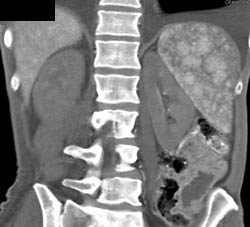

Small SMA and Celiac With Gastric Emphysema